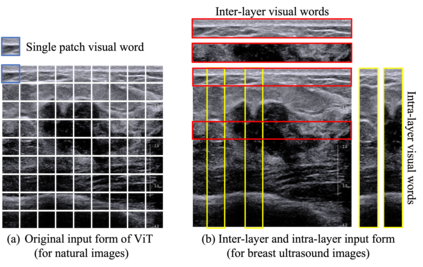

Ultrasonography is an important routine examination for breast cancer diagnosis, due to its non-invasive, radiation-free and low-cost properties. However, it is still not the first-line screening test for breast cancer due to its inherent limitations. It would be a tremendous success if we can precisely diagnose breast cancer by breast ultrasound images (BUS). Many learning-based computer-aided diagnostic methods have been proposed to achieve breast cancer diagnosis/lesion classification. However, most of them require a pre-define ROI and then classify the lesion inside the ROI. Conventional classification backbones, such as VGG16 and ResNet50, can achieve promising classification results with no ROI requirement. But these models lack interpretability, thus restricting their use in clinical practice. In this study, we propose a novel ROI-free model for breast cancer diagnosis in ultrasound images with interpretable feature representations. We leverage the anatomical prior knowledge that malignant and benign tumors have different spatial relationships between different tissue layers, and propose a HoVer-Transformer to formulate this prior knowledge. The proposed HoVer-Trans block extracts the inter- and intra-layer spatial information horizontally and vertically. We conduct and release an open dataset GDPH&GYFYY for breast cancer diagnosis in BUS. The proposed model is evaluated in three datasets by comparing with four CNN-based models and two vision transformer models via a five-fold cross validation. It achieves state-of-the-art classification performance with the best model interpretability.